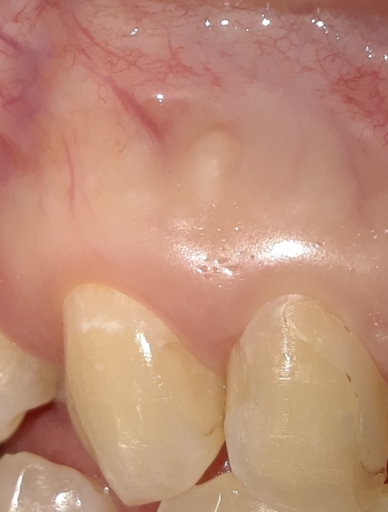

Hi,I reinjured one of my front teeth that was previously injured after a fall and was pushed back in my mouth 1 yr ago. I had it positioned back into place, got a root canal done and had splinter over it. But 2 weeks ago I reinjured the tooth and it got pushed back in my mouth again. It got positioned back in place but this time it hung lower than other teeth and is loose. Dentist said I have root reabsorption and should get it pulled. Is my roots broken? Can my tooth be tightened back up again and pushed upwards into gums? Or must I get it extracted? Will my tooth eventually fall out anyways if I decide to keep it? I really want it saved.